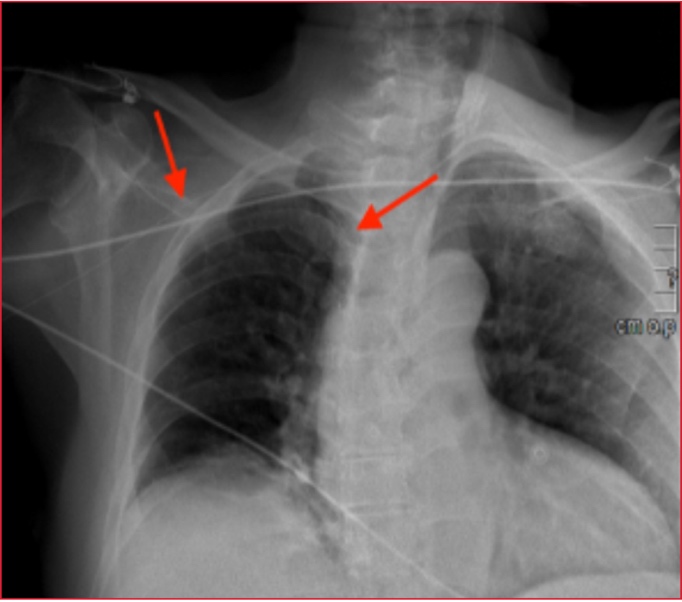

Paciente de 75 años, en el que se procedió a canalización de catéter venoso central de acceso periférico, con dificultad, con perdida de la guía metálica en el interior de la vena basílica. Se realizó radiografía de tórax, donde se objetivó la guía metálica llegando hasta la cava superior (Figura 1, flechas rojas) Se completó el estudio con tomografía computarizada, observándose progresión de la guía hasta la cava inferior, tanto en corte coronal (Figura 2, flecha roja) como en la vista axial (Figura 3, flecha roja). Se comentó el caso con Cirugía Vascular, que procedió a disección y venotomía basílica y extracción de guía sin complicaciones.